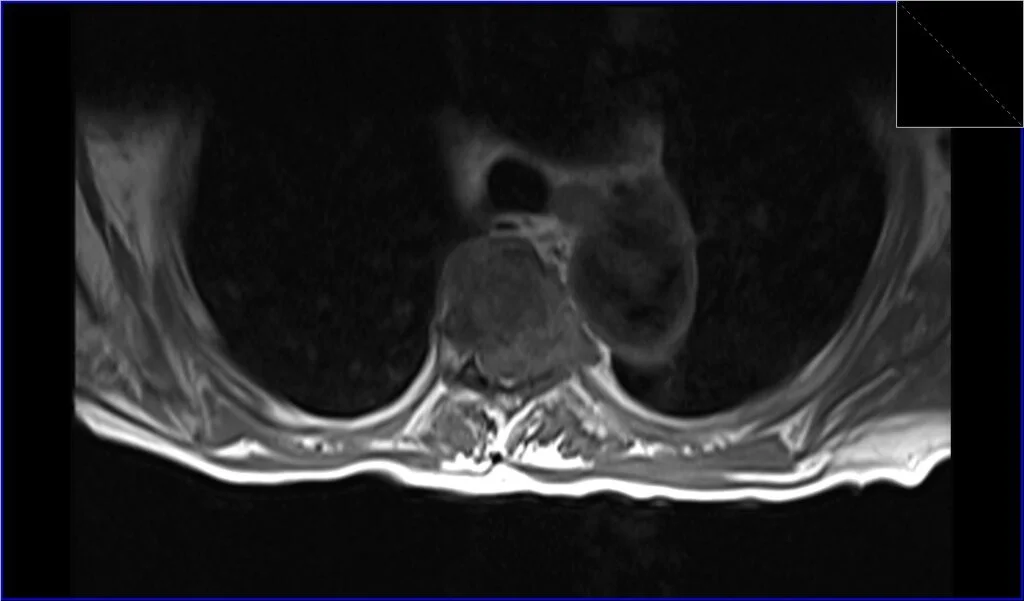

T2 TSE axial image shows Metastatic Spinal Cord Compression

T1 TSE axial image shows Metastatic Spinal Cord Compression